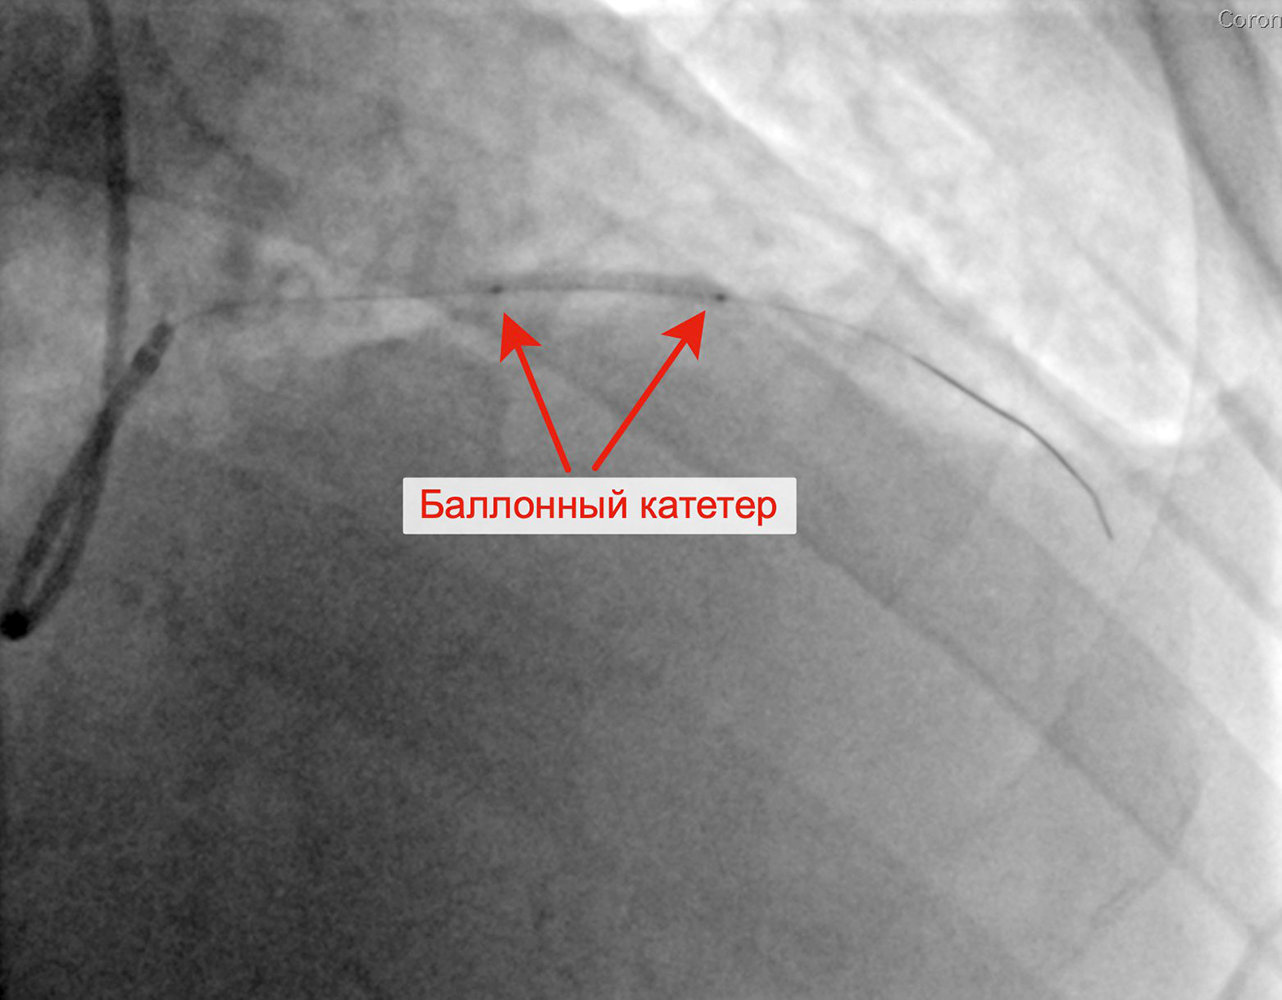

Вторым этапом в январе 2023 г. принято решение о проведении пациенту с персистирующей формой ФП, ГКМП, сохраняющейся клиникой стенокардии напряжения, известной коронарной анатомией, многососудистым поражением коронарного русла баллонной ангиопластики и стентирования крупной диагональной артерии (ДА) (1 стент с лекарственным покрытием). При контрольной ангиографии: стент и ДА проходимы, позиционирование стента адекватное, диссекции или остаточного стеноза в стентированном сегменте ДА нет, кровоток TIMI 3 по ДА и всем ее ветвям.

Стенозы диагональной артерии Выполнена баллонная ангиопластика ДА

Выполнено позиционирование и имплантация стента в ДА Финальный результат стентирования ДА